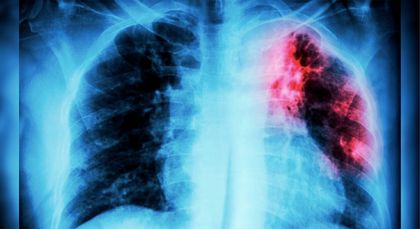

Antioquia, el primer departamento en implementar pruebas vanguardistas para el diagnóstico rápido de tuberculosis

El Oriente es la segunda subregión de Antioquia con más casos de tuberculosis